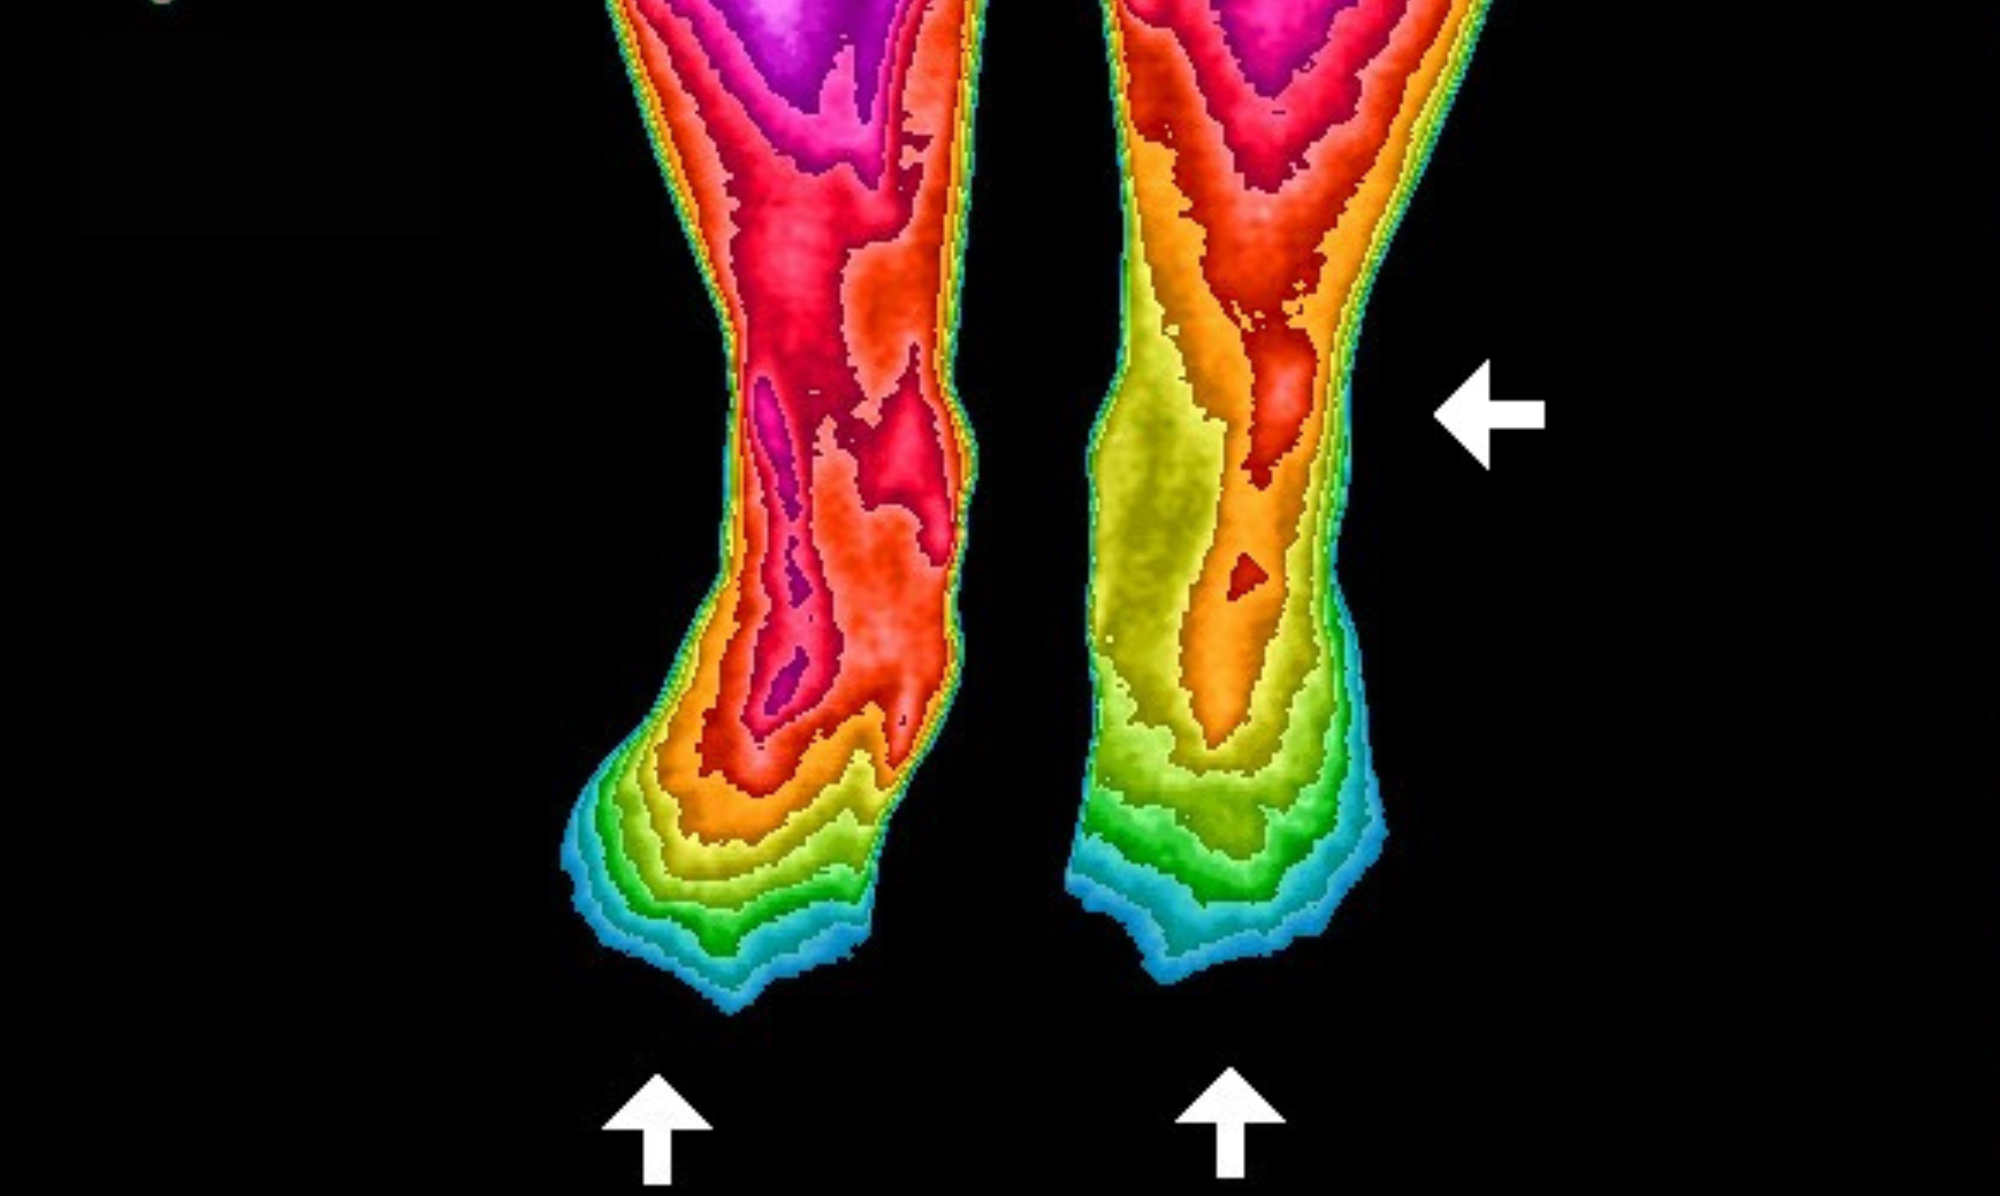

More than 26 scientific studies have examined grounding's positive effects on the human body. The infrared images shown here demonstrate blood flow changes after using our Earthing Mattress Cover for two weeks. Initially, toe circulation was nearly non-existent. Following the grounding period, healthy circulation returned to normal levels. This represents just one example from the extensive research conducted.